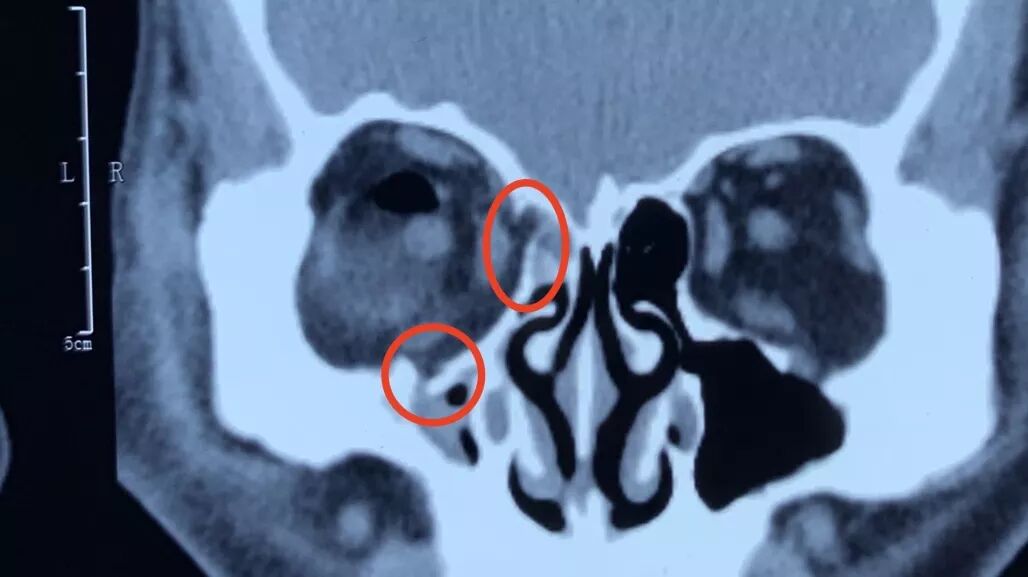

肖主任介绍说,爆裂性骨折,复视,眼球运动障碍和眼球凹陷是主要症状和体征。复视程度与骨折部位及范围大小有关。眶底骨折多出现垂直位复视,常主诉下楼梯或阅读困难,眶内壁骨折多出现水平位复视。通过眼眶CT可以一目了然的了解有无骨折及其部位,范围,有无软组织或肌肉嵌顿等。

上图可见下直肌后段肌腹嵌顿